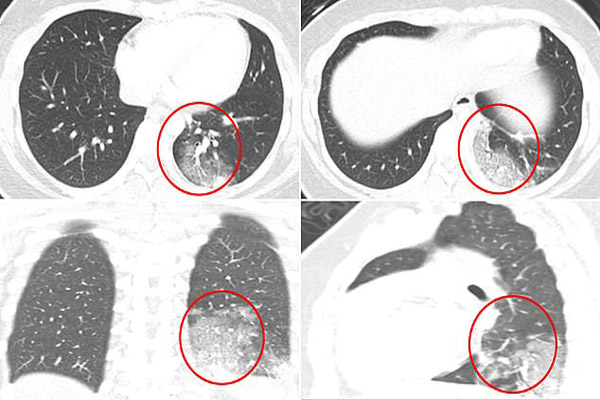

این تیم از بیمارستان کودکان بوستون ، سی تی اسکن از موارد کودکان مبتلا به COVID-19 را برای دیدن نتایج و وضعیت ظاهری ریه ارزیابی کردند.

در یک مطالعه از 20 کودک تقریبا دو سوم آنها مبتلا به التهاب ریه ای شده بودند.

بخش دیگری از کودکان با مشکلات تنفسی شدید روبرو می شوند و کیسه های هوای موجود در ریه آنها مملو از مایعات می شود که بسیار خطرناک است.

در تصاویر سی تی اسکن ریه کودکان مشخص است که ریه آنها تحت تاثیر ویروس کرونا کدرتر شده است.